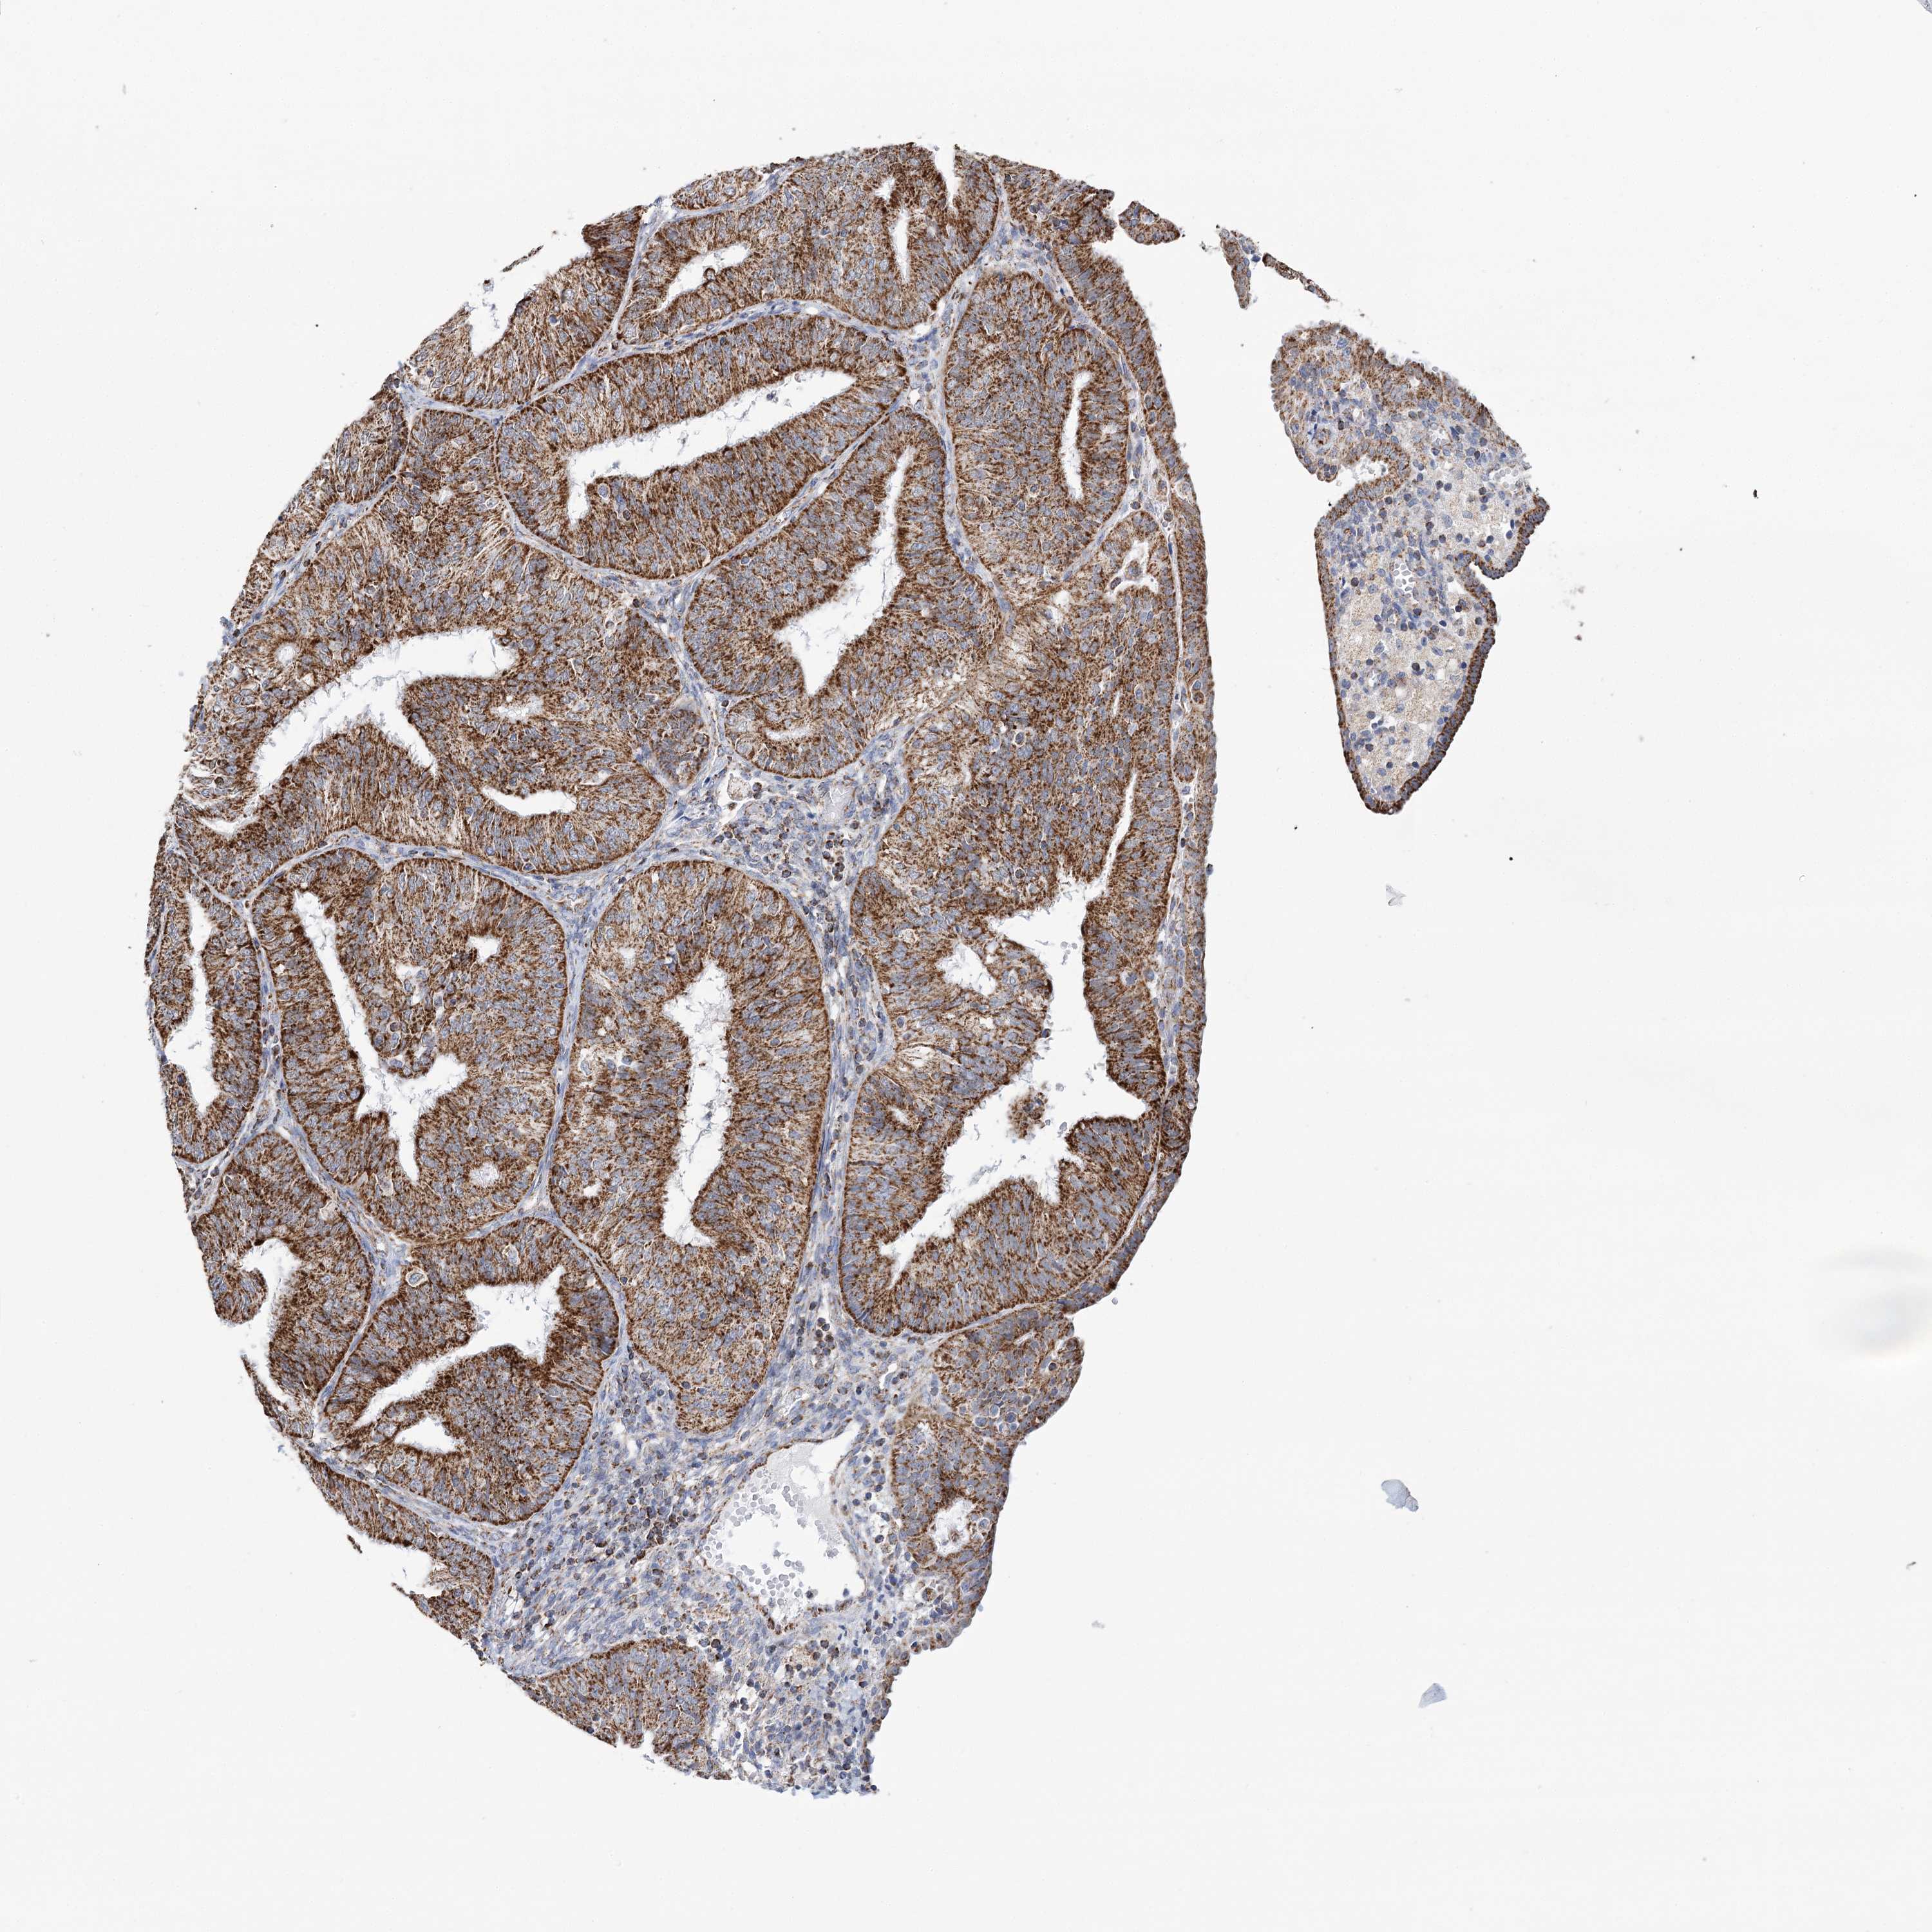

ENDOMETRIAL CANCER - Protein expressioni

A mouse-over function shows sample information and annotation data. Click on an image to view it in a full screen mode. Samples can be filtered based on level of antibody staining by selecting one or several of the following categories: high, medium, low and not detected. The assay and annotation is described here.

Note that samples used for immunohistochemistry by the Human Protein Atlas do not correspond to samples in the TCGA dataset.

Antibody stainingi

Antibody staining in the annotated cell types in the current human tissue is reported as not detected, low, medium, or high, based on conventional immunohistochemistry profiling in selected tissues. This score is based on the combination of the staining intensity and fraction of stained cells.

Each image is clickable and will lead to virtual microscopy that enables deeper exploration of all samples and also displays staining intensity scores, fraction scores and subcellular localization as well as patient and tissue information for each sample.

Antibody HPA032060

Antibody HPA032062

Antibody CAB034116

Staining

High

Medium

Low

Not detected

Intensity

Strong

Moderate

Weak

Negative

Quantity

>75%

75%-25%

<25%

None

Location

Nuclear

Cytoplasmic/membranous

Cytoplasmic/membranous,nuclear

Adenocarcinoma, NOS

Adenocarcinoma, metastatic, NOS